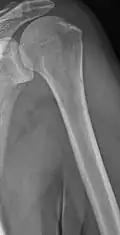

Humerus with multiple myeloma lesions -

Same humerus before, with just subtle lesions

The diagnostic examination of a person with suspected multiple myeloma typically includes a skeletal survey. This is a series of X-rays of the skull, axial skeleton, and proximal long bones. Myeloma activity sometimes appears as "lytic lesions" (with local disappearance of normal bone due to resorption) or as "punched-out lesions" on the skull X-ray ("raindrop skull"). Lesions may also be sclerotic, which is seen as radiodense.[76] Overall, the radiodensity of myeloma is between −30 and 120 Hounsfield units (HU).[77] Magnetic resonance imaging is more sensitive than simple X-rays in the detection of lytic lesions. An MRI may supersede a skeletal survey, especially when vertebral disease is suspected. Occasionally, a CT scan is performed to measure the size of soft-tissue plasmacytomas. Nuclear Medicine Bone scans are typically not of any additional value in the workup of people with myeloma (no new bone formation; lytic lesions not well visualized on nuclear bone scan).

Multiple myeloma in the upper arm -